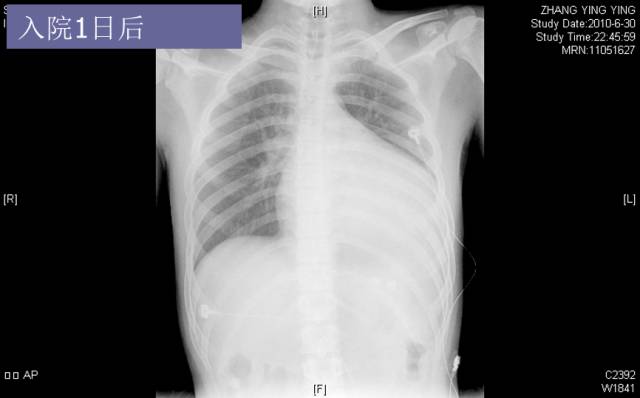

入院胸片

► 7月后复查:心脏缩小,心功能好转